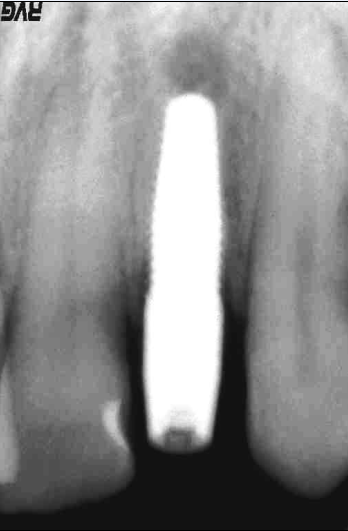

Lo scopo del presente lavoro quello di dimostrare i reali vantaggi che una tecnica delicata, come quella post-estrattiva offre nel riabilitare protesicamente un settore ad alta rilevanza estetica. Il paziente in esame presentava una frattura coronale del 22 devitalizzato, con lesione granulomatosa peri-apicale. Su richiesta del paziente veniva applicata una corona provvisoria e programmato per un impianto post-estrattivo. Le condizioni cliniche del paziente erano buone per cui si procedeva alla pianificazione del caso. Pianificazione che prevedeva, lestrazione del 22 con asportazione del granuloma peri-apicale, disinfezione, cruentazione dellalveolo, ed applicazione di un impianto Nobel-Direct (3.5 x 13 mm). La valutazione intra-operatoria dellaltezza alveolare, della distanza crestale vestibolo-palatale e mesio-distale, facevano propendere per linserimento di un impianto Nobel-Direct della dimensione 4.3 x 13 mm senza fresatura alveolare, ma semplicemente avvitandolo nellalveolo e raggiungendo una forza di serraggio > di 45 N. Preparare il sito implantare per una maggiore profondit avrebbe creato problemi per lasse implantare determinando una eccessiva vestibolarizzazione del moncone. Si procedeva allapplicazione ed alladattamento del provvisorio dopo una piccola correzione del moncone. Nota importante da sottolineare il perfetto adattamento del provvisorio, non solo al pilastro implantare ma anche alla mucosa gengivale, dove soprattutto nellimplantologia post-estrattiva lemergenza dellimpianto non sar mai perfettamente aderente n alla cresta alveolare, quasi sempre a sezione ovalare, n alla mucosa gengivale. Il sigillo mucosale garantisce la formazione ed il mantenimento di quel coagulo ematico che andr a colmare il gap tra osso, impianto e corona, impedendo laccumulo di residui alimentari e di placca, che minerebbero sicuramente questa zona critica. Si comprende pertanto che il provvisorio non deve invadere uno spazio che non gli compete, ma deve occupare sicuramente quello spazio che prima competeva alla corona riproducendo perfettamente gli stessi rapporti con i tessuti limitrofi. Al paziente veniva consigliata una copertura antibiotica (Amoxicillina cpr 1 gr/12 ore x 5 gg,; Efferalgan cpr 1 cpr alloccorrenza; Dentosan collutorio 0,20% - 3-4 sciacqui al die x 10 gg) evitare sovraccarichi masticatori, di poter incidere ma di non strappare i cibi. Il paziente veniva controllato dopo 7 giorni, ad 1 mese ed al terzo mese, periodo questultimo in cui si procedeva ad un controllo rx endorale alla preparazione del pilastro con ribasatura del provvisorio. Dopo circa 7 giorni si rilevavano le impronte di precisione e quindi si finalizzava il lavoro. Possiamo ritenerci soddisfatti del risultato finale, sia clinico, che radiografico ed estetico, considerando le difficolt presentatesi durante lintervento. Tra queste annoveriamo sicuramente lestrazione del residuo radicolare, devitalizzato, con granuloma peri-apicale e lesiguit della corticale vestibolare, che doveva essere assolutamente conservata. Il risultato estetico finale, tessuti molli e corona dentaria, sicuramente soddisfacente, e deriva da una cura minuziosa dei particolari chirurgici e protesici, sempre nel rispetto massimo dei tessuti.

Il paziente in esame stato sottoposto ad estrazione del residuo radicolare del 22 con asportazione di granuloma peri-apicale ed inserimento contestuale di una fixture monofasica (Nobeldirect) con protesi fissa provvisoria. Il caso stato completato con protesi fissa oro-ceramica dopo tre mesi dall'intervento.